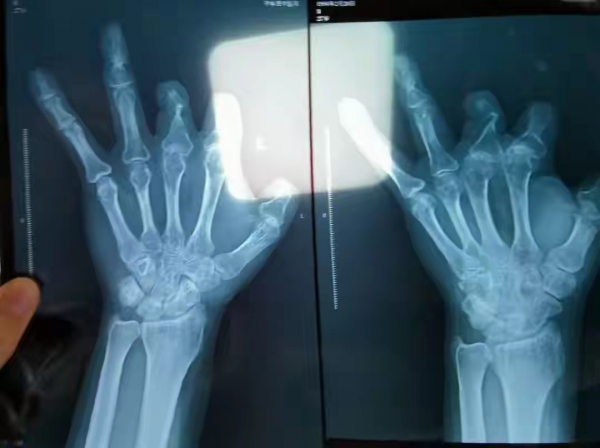

直到2021年12月,有人提醒他,这个昂贵的血管吻合器,在X光片上是能看到的,让他去拍个片看看。王海森半信半疑,在老家医院拍了左手X光片,结果一看,手术部位干干净净,根本没有所谓的吻合装置!

"带着不锈钢针的器材,怎么可能消失?唯一的可能就是,手术时根本就没给我用!"王海森又气又恨,当即向警方报了案。

而王海森不是第一个受害者。早在2017年,河南中牟的彭先生,因为四根手指被切断,在郑大一附院做了12小时的断指再植手术,收费单显示,仅微血管吻合装置就用了6个,花费10.08万元,总材料费高达14.3万。可术后手术效果很差,拍X光片同样发现,这6个天价器材,一个都没在体内!